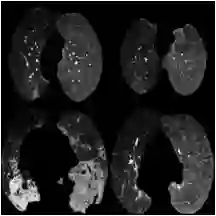

The pandemic resulted in vast repositories of unstructured data, including radiology reports, due to increased medical examinations. Previous research on automated diagnosis of COVID-19 primarily focuses on X-ray images, despite their lower precision compared to computed tomography (CT) scans. In this work, we leverage unstructured data from a hospital and harness the fine-grained details offered by CT scans to perform zero-shot multi-label classification based on contrastive visual language learning. In collaboration with human experts, we investigate the effectiveness of multiple zero-shot models that aid radiologists in detecting pulmonary embolisms and identifying intricate lung details like ground glass opacities and consolidations. Our empirical analysis provides an overview of the possible solutions to target such fine-grained tasks, so far overlooked in the medical multimodal pretraining literature. Our investigation promises future advancements in the medical image analysis community by addressing some challenges associated with unstructured data and fine-grained multi-label classification.